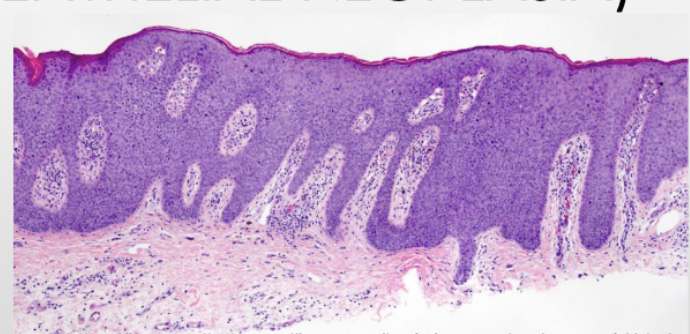

the following describes what condition:

• Slow growing; affects glans penis or prepuce

• Asymptomatic until ulcerated

• May have cauliflower appearance, can be ulcerated

• Metastasis to inguinal lymph nodes can occur early on

squamous cell carcinoma